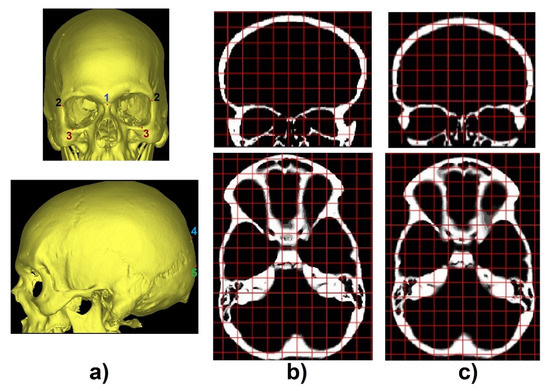

To identify the transverse and coronal angles through the 3D CNN, 101 volumetric images, from the 195 segmented images, were selected to create a database. The first step was to identify cephalometric landmarks to help align the predicted labels Figure 3a. In the coronal plane, we selected the 1-crista galli, 2-frontozygomatic suture, and 3-orbitale while in the sagittal plane, we selected 4-lambda and 5-opistocranion. To identify these points and make the necessary alignment, two grids were generated as a reference in the transverse and coronal planes. A number of slices were verified, and the necessary adjustments were performed (Figure 4b,c).

Figure 4.

(a) Identification of cephalometric landmarks in coronal (top) and sagittal plane (bottom), (b) CT slices misaligned, and (c) CT slices after the alignment procedure (coronal plane-top and transverse plane-bottom).

After the alignment, for each of the 101 images, a set of 441 images with inclination angles from −5° to 5°, with 0.5° increments, along the coronal and transverse planes was created. In total, 44541 images were created and were divided into 21 labels. These labels represented the 0.5° of variation in the coronal and transverse planes from −5° to 5°, as shown in Figure 5.